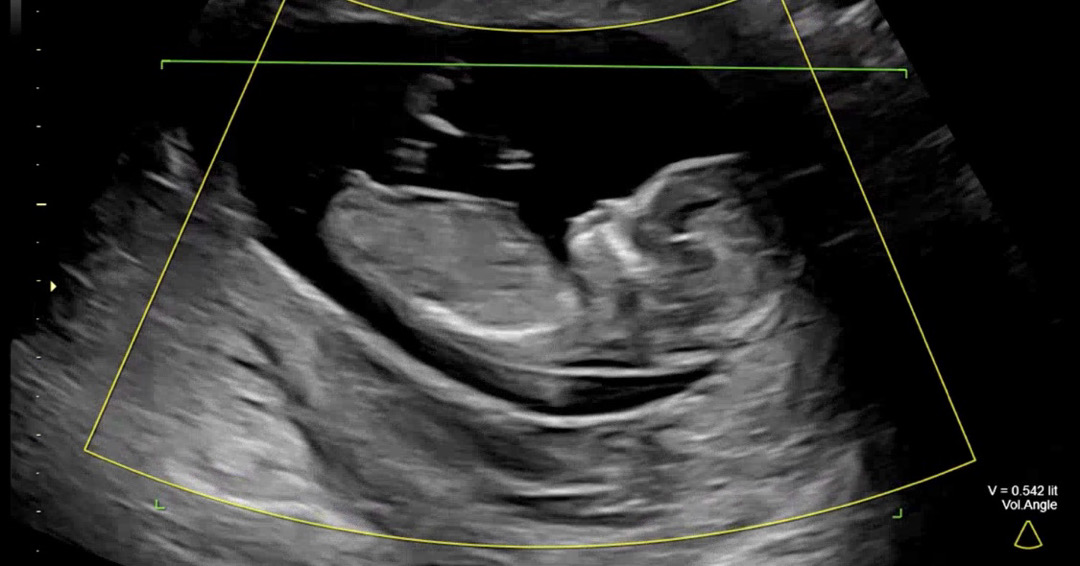

12주 초음파 각도법

각도법 한번 봐주세요~~!ㅎㅎ

각도로는 딸에 한표요~! 12주면 아직 확실한 주수는 아니어서^^